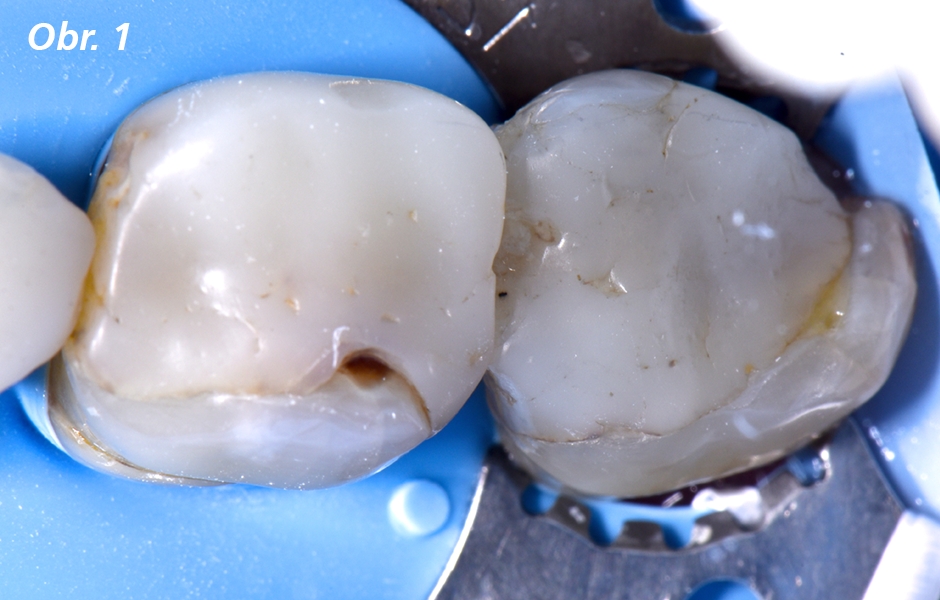

Do mé ordinace se dostavila 71letá pacientka požadující výměnu nevyhovující, značně rozsáhlé kompozitní výplně na dolním pravém prvním a druhém moláru (zuby 46 a 47). Přirozená korunka si ještě udržela malé množství zbytkové struktury a pacientka si nepřála další odstranění zubní hmoty. Z finančních důvodů si pacientka také nepřála žádné protetické ošetření, např. v podobě keramických náhrad. Pacientce byla doporučena přímá komplexní pryskyřičná onlej vyžadující funkční i „nefunkční" redukci hrbolku. U tohoto nekonvenčního přístupu bylo důležité, aby tvar okluze zohledňoval silné i slabé stránky jak výplňového materiálu, tak i zbytkové struktury zubu.

Situace před ošetřením vykazující rozsáhlé výplně a minimální zbytkovou zubní strukturu